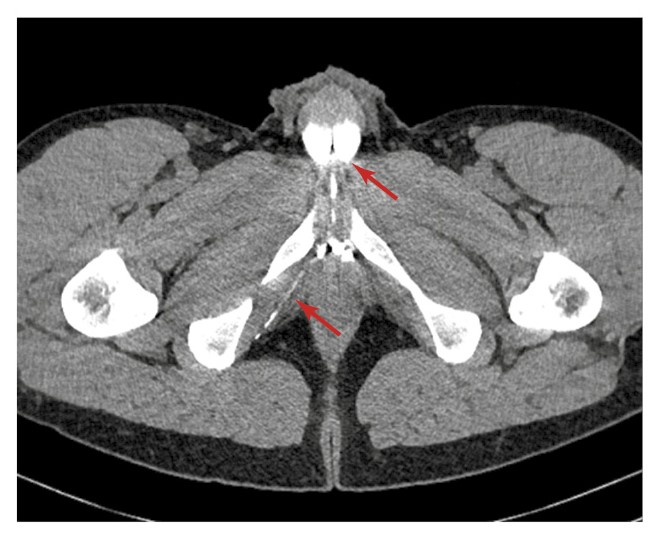

С целью подтверждения венозной утечки и оценки венозной анатомии половой системы пациенту проведена МСКТ-кавернозография. Фармакологическую стимуляцию осуществляли посредством введения 10 мкг простагландина интракавернозно. Получены изображения в нативную фазу (до введения контрастного вещества), а также через 30 с, 1, 3 и 5 мин после интракавернозного введения контрастного препарата (йогексола 350 мг/мл, 50 мл). По данным КТ в области наружной и внутренней поверхностей правой лобковой кости определяются множественные гиперденсивные структуры, вероятно, эмболизационные спирали (рис. 2).

Рис. 2. Данные МСТК-кавернозографии больного К. Стрелкой указаны гиперденсивные инородные структуры (вероятно, спирали) в области правой лобковой кости.

Размеры, форма и ход кавернозных тел обычные. Отток контрастного препарата нарушен. На 30-й секунде определяется наличие минимального сброса контрастного препарата в перипростатическое сплетение через вену левой ножки ПЧ. На 1-й минуте отмечаются умеренное контрастирование вен в области левой ножки ПЧ и существенный сброс контрастного препарата через вены правой ножки ПЧ и вены тазового сплетения справа (рис. 4).

Рис. 4. Данные МСКТ-кавернозографии больного К. Стрелкой указана утечка контрастированной крови из кавернозных тел в области ножки ПЧ через вены правого кавернозного тела в тазовое сплетение.